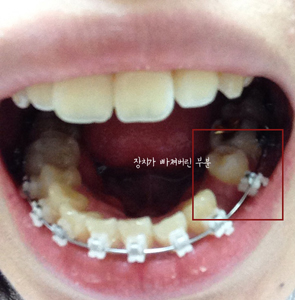

그런데 월치료날이 되기 전에 장치 하나가 탈락하는 바람에 중간에 한번더 치과에 다녀왔어요..

장치 탈락의 사건 전말은,,,

아침에 뜬눈으로 양치질을 부ㅡ아앙 하고있는데 나도 모르게 칫솔모를 씹은거에요 ,, 나름 조심조심 한다고 했는데

아직적응중인지라 우직했는데 칫솔모인데 괜찮겠지 했어요 ,, 근데 덜렁덜렁,,,, 장치가 떨어져버린겁니다. ㅜㅜ

힝 나의 소중한 킬본교정장치에 이런 스크레취가 일어나다니,, 장치가 떨어져버려서 그날은 점심,저녁도 조심조심 먹고

다음날 가서 바로 다시 장치 달으러갔어요,,

치과 도착후 장치를 살펴보시면서 말씀해주시기를 장치가 처음부터 붙여지기를 튼튼하게 붙여지지 않았다고 하시더라구요

이렇게 장치 재부착을 완료하였습니다.